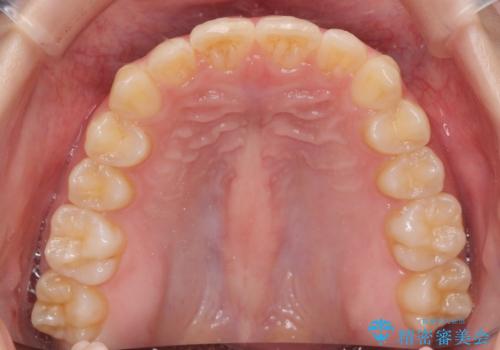

- 突出感のある、前歯の矯正治療を求めて来院されました。

軽度な突出・ガタつきを26枚・約半年の矯正治療期間で計画するインビザラインモデレートプランで治療を始めて行きます。

約半年といった短期間で、前歯の角度やガタつきを改善することができました。